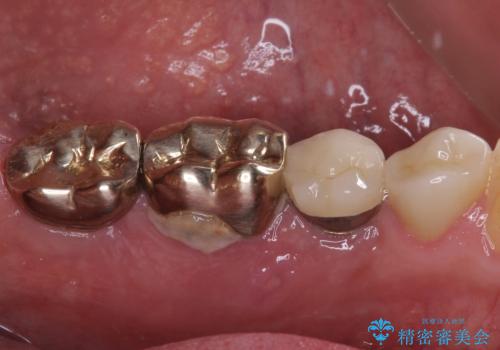

- 奥歯が割れてしまい、抜歯が必要となった患者様です。

以前にも歯が割れてインプラント治療を行いましたが、抜歯してからインプラント埋入→仮歯装着までに半年以上を要し、その間に残された歯への負担が大きくなり、セラミッククラウンが破折したことがありました。

そのため、当院に新しく導入した手法により、抜歯をした日にインプラントを埋入し、そのままを仮歯を装着することで、他の歯への負担を軽減する計画を立てました。